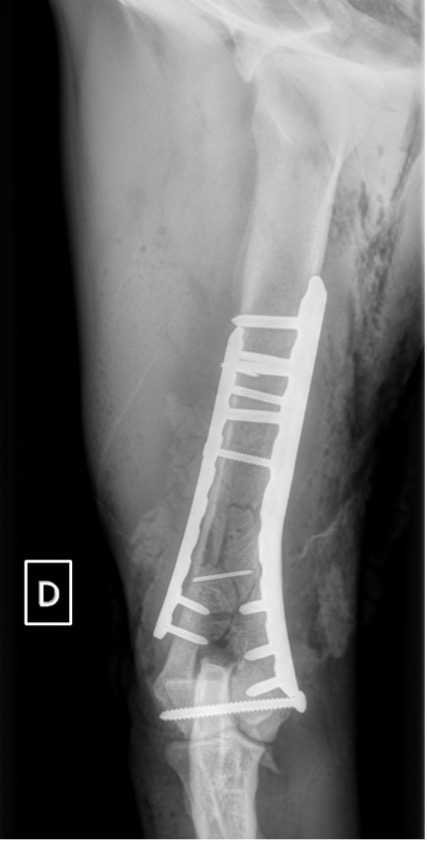

Exemple 2 :

Figure 4 : Pré-Op

Figure 5 : Post-Op Immédiat

Notre préférence va vers le placement de deux plaques humérales : une médiale de la plus grande taille possible et l’autre latérale, généralement d’une taille inférieure à la première. Dans l’exemple 1 (chat européen), une plaque de 2 mm est utilisée médialement et une plaque de 1,5 mm latéralement. Dans l’exemple 2 (chien Malinois), une plaque de 3,5 mm est utilisée médialement et une plaque de 2,7 mm latéralement.